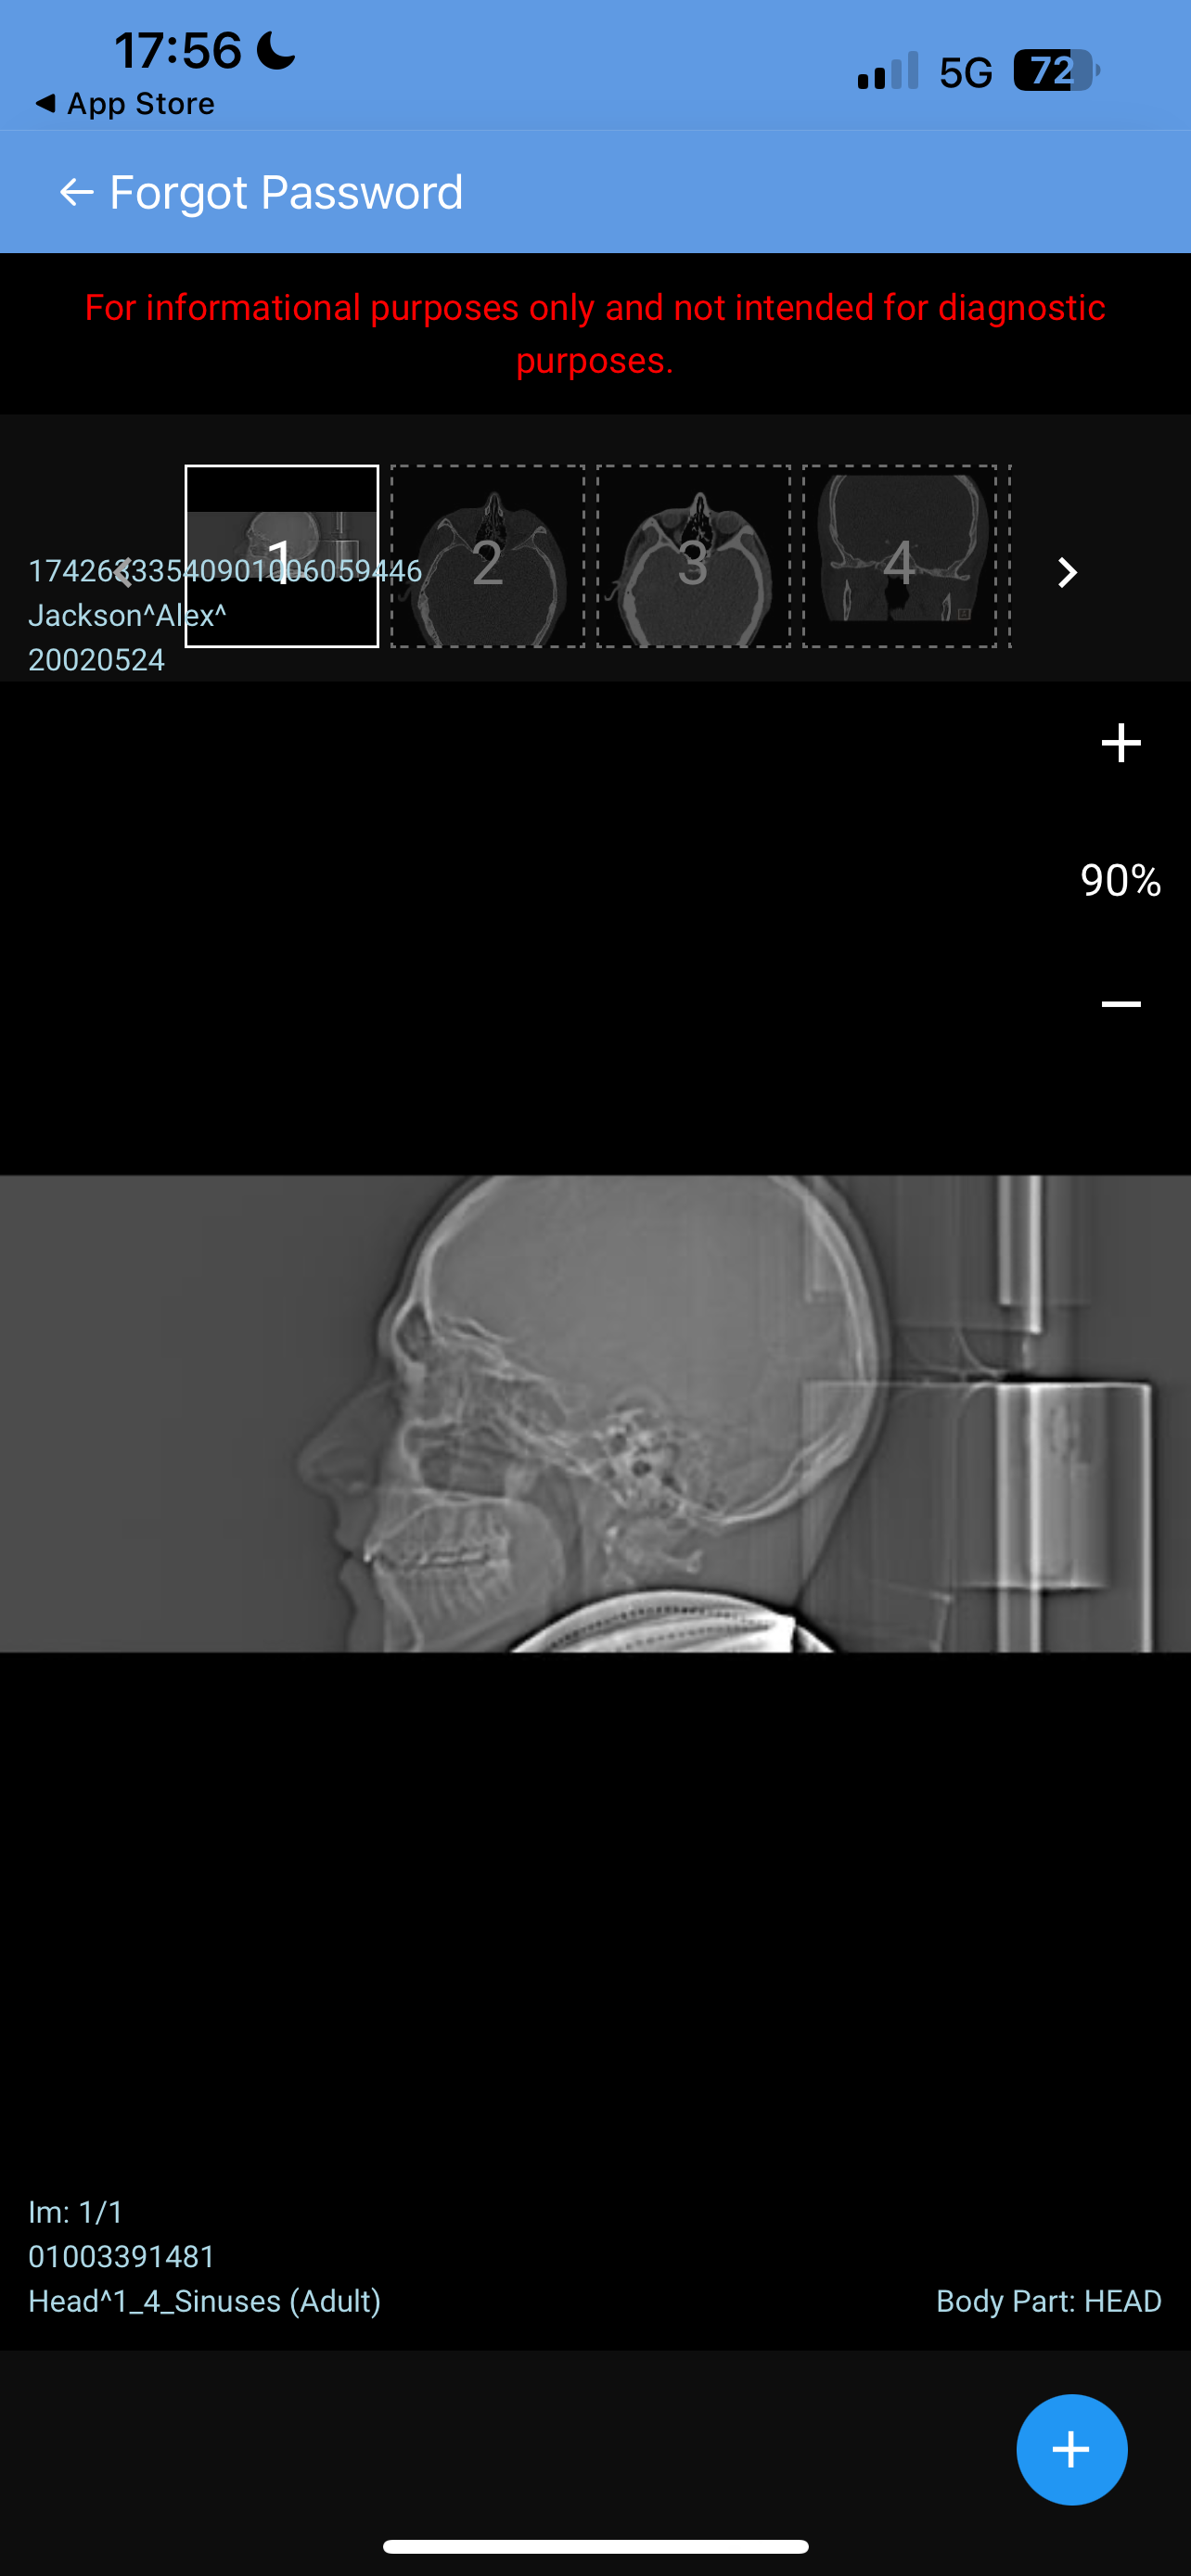

Hello, I’m looking for advice on genioplasty vs DJS. I was planned for a genio 7mm horizontal and squaring of chin on may 11th. I got a second opinion because I thought the oralmaxillofacila surgeon doing my genio might have been downplaying my mandible/maxilla recession. The second opinion oomfs surgeon said that genio would only be a camouflage and for my high expectations, might disappoint me, and I’m starting to think it will. My midface is flat and my mandible from side profile looks short and awful. The problem I have is DJS is a huge commitment for a bigger gain in a year-year and a half time. It’s a lot to take in. But I really don’t want to live my whole life with recessed jaws, I don’t want a soft youthful boyish look especially because I’m getting into my mid 20s, I hate my side profile a lot. Genio will help but I’m extremely worried I’ll be really disappointed, and I can’t really go back if I commit. Looking for advice on if I should go with the genio, see improvement now (which I care a lot about) and get a rhino/septoplasty to fix my deviated septum and be capped by by midface/mandible recession but decently improved, or If I should look awful for another year and a half with braces and my current recession but have the functional and aesthetic benefit of djs at the end. I have extremely bad breathing issues especially during exercise and pretty bad sleep issues, but I don’t know how much to that is down to allergies/deviated septum as opposed to airway issues. I just don’t know what to do, I’ll include my ceph/ct scans and side/front profile photos, would really appreciate guidance on what to do, was thinking of frauding with filler for a year before getting djs, or getting real structural change through rhino braces and genio that would all be down within 7-9 months, thankyou .

• IMG_3956.jpeg

IMG_3956.jpeg

958.3 KB · Views: 0